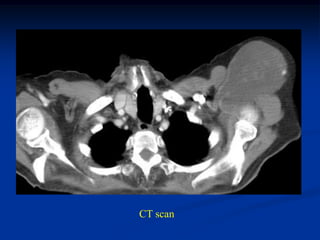

Case #1171

9 year male with desmoid tumor posterior axilla

tumor

CT scan

Axial T-2 MRI

Photomic